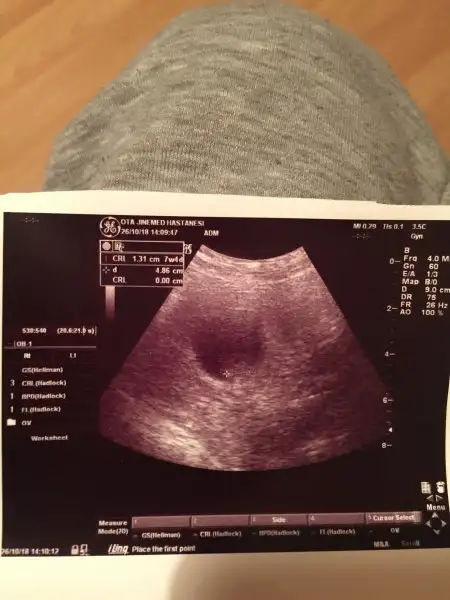

Kuzlar aşk olsun yokmu şimdi hiç bilgisi olan bu tahlillerden anlayan![]()